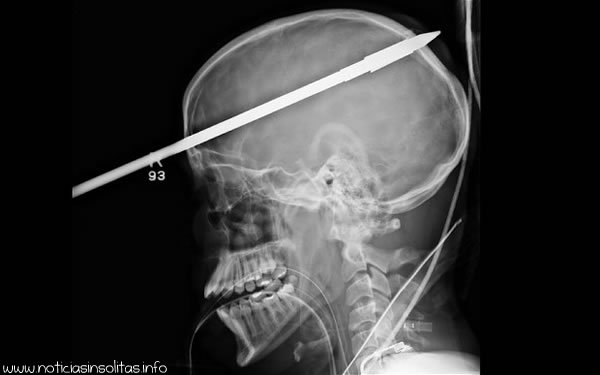

Yasser López, de 16 años, puede sentirse muy afortunado de haber sobrevivido tras el accidente ocurrido en un lago de Florida donde se encontraba pescando con un amigo. El amigo que le acompañaba se le disparó por error un arpón de pesca y este impactó sobre la cabeza de López. López enseguida perdió la consciencia y fue trasladado en helicóptero al Jackson Memorial Hospital de Miami, donde los médicos tuvieron que serrar parte de la lanza para que pudiera caber en el escáner. Milagrosamente, la lanza se dirigió directamente a través de su cerebro, pasando muy cerca de su ojo derecho y perforando la parte derecha de su cerebro. El neurocirujano Ross Bullock, afirma que López tuvo mucha suerte, ya que la lanza no llegó afectar los vasos sanguíneos del cerebro.

La radiografía reveló que la punta de la lanza era de tornillo, buscaron la manera de desenroscar la lanza sin tener que arrastrarla a través de su cerebro, y finalmente tras tres horas de operación lograron retirarla sin causar más daños al paciente. Ahora López sufre amnesia post-traumática y no recuerda nada de lo que ocurrió aquel día, y también tiene problemas para mover el lado izquierdo de su cuerpo, aunque los médicos creen que podrá recuperarse completamente.